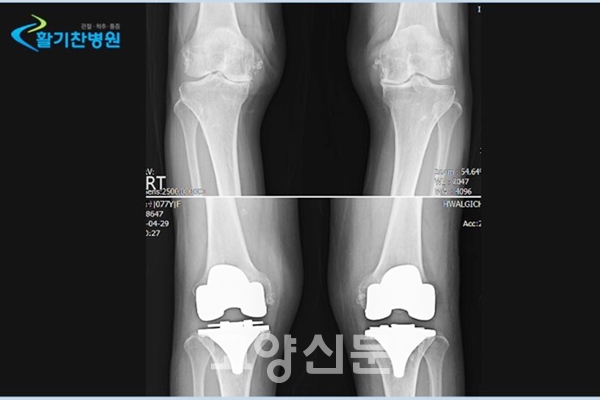

무릎 관절염 환자 중 상체가 비만이고 다리가 ‘O자형’으로 휘어져 있는 경우가 많다. 이는 무릎관절이 체중을 오랜 시간 견디다 못해 안쪽의 관절 연골이 닳아 없어지면서 다리의 변형이 진행되는 것이다. 자신의 다리가 ‘O자형’으로 휘어져 있는지를 한번 살펴보고 미리 관절염에 대처하는 것이 좋다.

관절의 손상이 심하면 인공관절을 사용해 손상된 부위를 보완해주는 인공관절수술을 시행해야한다. 인공관절수술이란 인체에 무해한 인공 기구를 손상된 관절부위에 삽입해 수술하는 방법으로 통증을 완화해주고 관절의 운동 범위를 확보해주는 수술이다.

인공관절의 장점은 손상된 관절부위 대신 자신에게 알맞은 인공관절을 삽입해 수술 이후 좀 더 자연스러운 일상생활이 가능하다.

평소 퇴행성관절염으로 인한 O자형 다리의 엉거주춤한 걸음과 참을 수 없는 통증은 활동성과 자신감을 떨어뜨려 몸과 마음을 병들게 한다. 하지만 최근 인공관절수술을 통해서 말기 퇴행성관절염 환자도 등산과 같은 야외활동을 다시 시작하며 삶의 활력과 자신감을 되찾아 제2의 활기찬 노년을 누릴 수 있다.